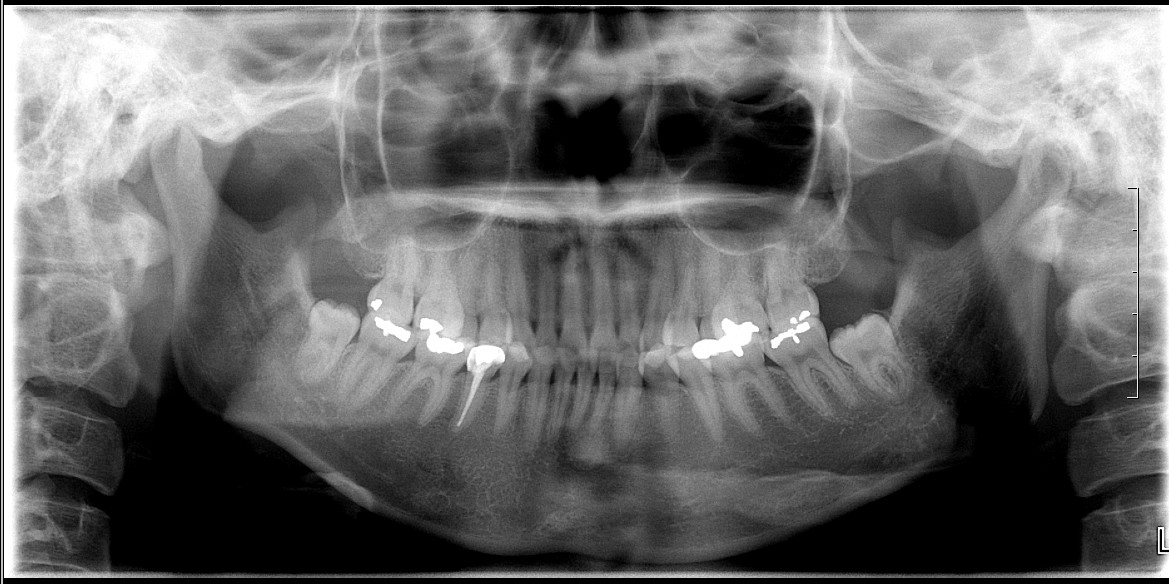

안녕하세요~ 저는 26살이고 지방에 거주하고 있습니다. 어렸을 때부터 앞니가 튀어나와 토끼 같다는 말을 들어오긴 했지만 돌출에 대해 딱히 고민해 본적 없이 지내왔었어요ㅠ 하지만 대학생활을 하고, 졸업사진을 찍...

돌출 개선될 수 있을까요

철사맨 선생님 안녕하세요~^^ 전부터 돌출된 입이 컴플렉스 였어요. 나이 드니까 더 두드러지는것 같아 속상하고 주위에서도 입을 가려야 이쁘다고 하고 ㅠㅠ 30대 초반인데 그동안 생각만 하고 있던 교정을 더 늦기...

무턱개선된다고햇는데 비교해주세여 해도되나여

거의 2년 7개월전에 교정시작했습니다.. 교정 다하면 무턱이 개선이된다고하셧는데여 제가 요즘 안물어봣는데 담에 월치료할때 물어봐서 저 개선된거에요 말해도되나요 아직두 앞니가 안들어갓는데여 치아를 좀깍는다...